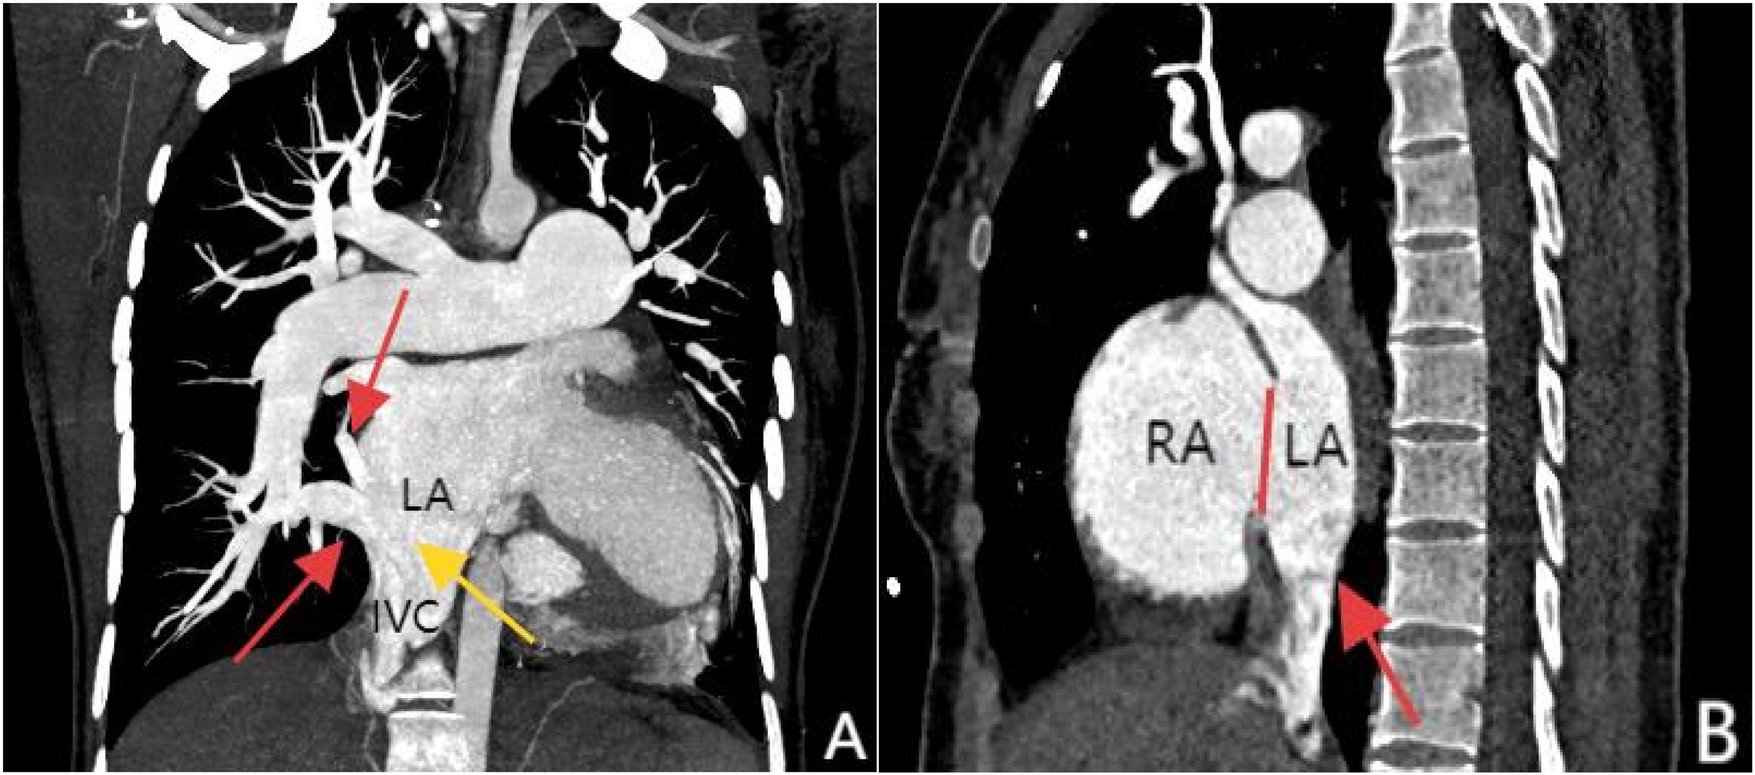

Transthoracic echocardiography (TTE) revealed an atrial septal defect (ASD) with a 3 cm opening (Figure 1), along with partial anomalous pulmonary venous drainage. Pulmonary artery systolic pressure (PASP) was 147 mmHg by measuring the tricuspid regurgitation spectrum using continuous Doppler., and severe tricuspid regurgitation, the inner diameter of the main pulmonary artery widened slightly, about 3 cm, left ventricular ejection fraction(LVEF) 69% were noted. Coronary CT angiography (CTA) confirmed these abnormalities and revealed a multi-fenestrated ASD (measuring 2.8 × 3.1 cm and 1.8 × 1.9 cm), the dorsal and basal segmental branches of the right inferior pulmonary vein drain abnormally into the inferior vena cava at its junction with the left atrium. Chest and abdominal CT angiography (CTA) further confirmed the IVC anomaly draining into the left atrium (Figures 2, 3). Right heart catheterization confirmed severe pulmonary hypertension, revealing a pulmonary artery pressure of 117/40 mmHg (mean 60 mmHg). While a full set of hemodynamic measurements including cardiac output was not obtained during the procedure, the documented pulmonary artery pressures were sufficient to establish the diagnosis of severe PAH and guide the initial therapeutic strategy (Figure 4).

Figure 3

Panel (A), coronal MIP reconstruction, shows that the branches of the right inferior pulmonary vein—specifically the superior segment and basal segments (indicated by the red arrows)—drain into the inferior vena cava at its junction with the left atrium, while the inferior vena cava (marked by the yellow arrow) shows anomalous drainage into the left atrium. Panel (B), contrast-enhanced sagittal view, clearly demonstrates the drainage of the inferior vena cava into the left atrium (red arrow) and an atrial septal defect between the left and right atria (marked by the red line).